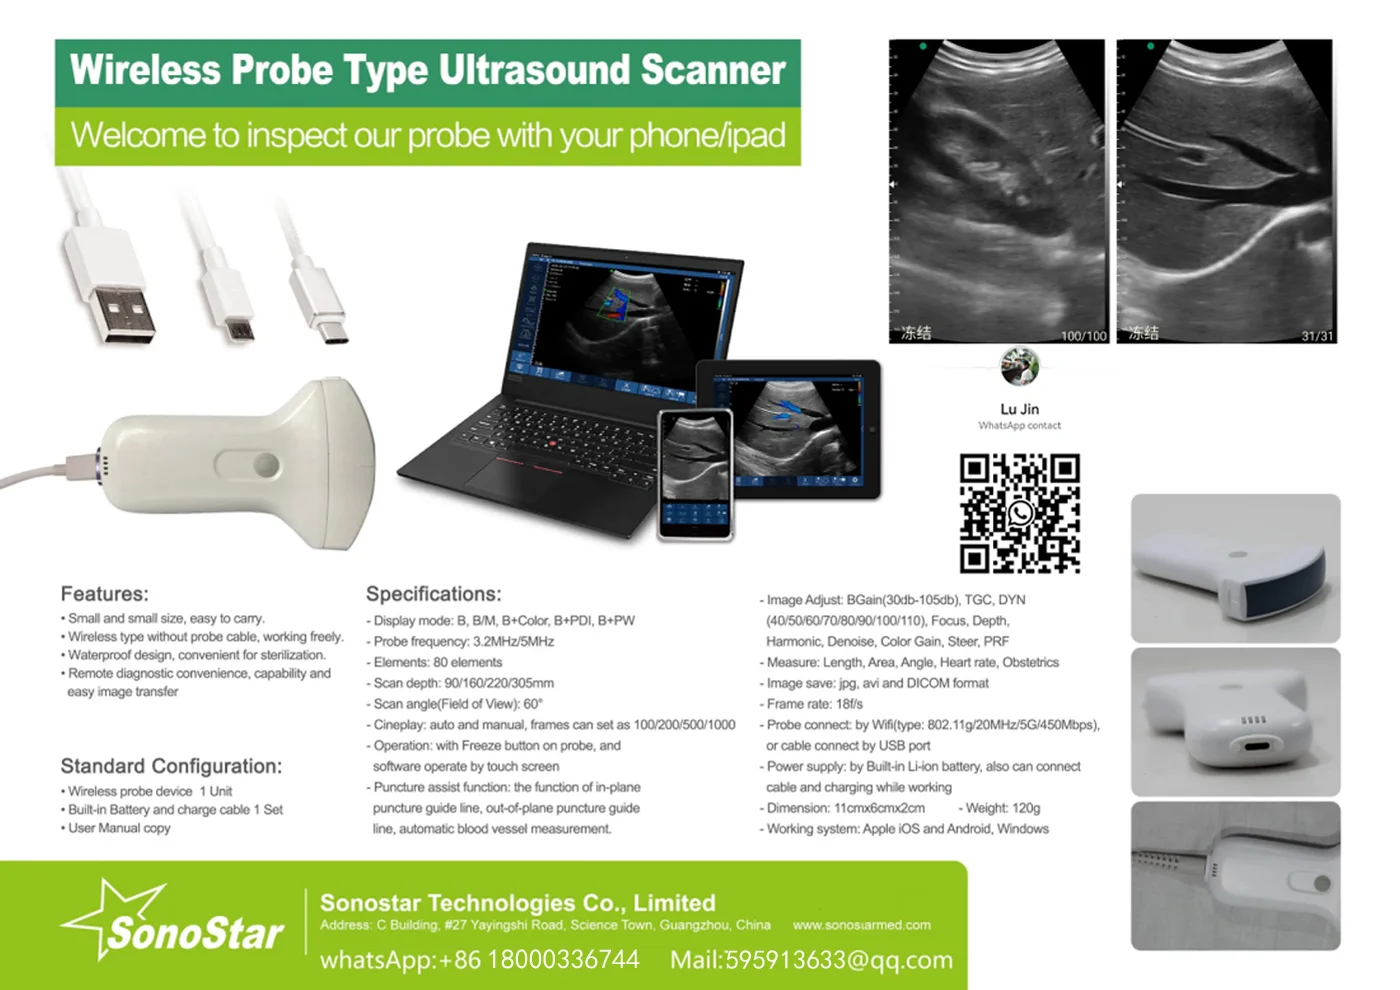

Linear Probe Parameters

-Scanning mode: Electronic array

-Display mode: B, B/M

-Probe element: 80

-Channel of RF circuit board: 16

-Frequency: 7.5MHz/10MH

-Scan depth: 20/40/60/100mm

-Head width: 40mm

-Image Adjust: BGain, TGC, DYN, Focus, Depth, Harmonic, Denoise, Color Gain, Steer, PRF

-Cineplay: auto and manual, frames can set as 100/200/500/1000

-Puncture assist function: the function of in-plane puncture guide line, out-of-plane puncture guide line, automatic blood vessel measurement.

-Measure: Length, Area, Angle, heart rate, Obstetrics

-Image save: jpg, avi and DICOM format

-Image frame rate: 18 frames / second

-Battery working time: 3~5 hours(according to different probe and whether keep scan)

-Battery charge: by USB charge or wireless charge, take 2 hours

-Dimension: 156×60×20mm

-Weight: 220g~250g

-Wifi type: 802.11g/20MHz/5G/450Mbps

-Working system: Apple iOS and Android, Windows 10 system

Standard Configuration:

-Main Host(probe) 1 Unit

-Internal Battery and charger 1 Set

-Non-slip lanyard

Convex Probe Pictures:

Linear Probe Pictures:

This machine can be used for both humans and animals: